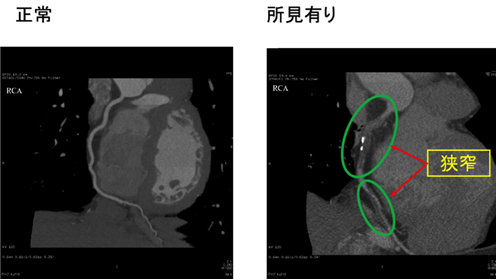

実際の検査で得られた右冠動脈の画像です。

左が正常、右が所見の有る画像になります。

左はきれいに造影剤入った血管が見えていますが、右は2カ所が染まらず、少し黒くなっています。つまり、この部分は造影剤が流れておらず、プラーク、血栓などによって狭窄しているのがわかります。